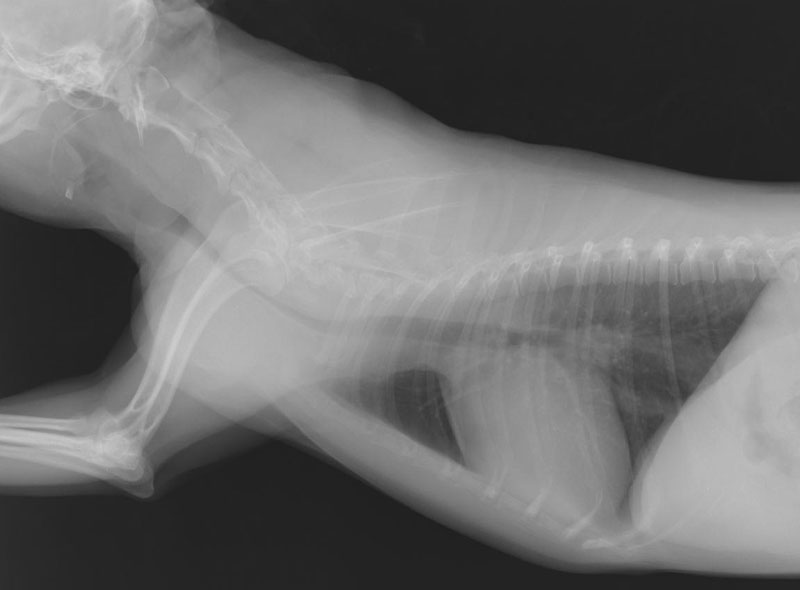

レントゲン検査

通常見ることのできない内臓の大きさや形、配置の変化を調べます。

心臓病、肺や気管・気管支の状態、腹腔内諸臓器の大きさや形の変化、腫瘍や結石の有無などがわかります。

肥大型心筋症・動脈血栓塞栓症

猫・中年齢以降で見られ、心臓の壁が分厚くなってしまう病気です。この病気は、だいぶ進んで、突然、後肢を引きずり、ギャアギャア泣き喚くなどの症状を呈して初めて気づくこともあります。こういった症状を呈する前に検診でそのリスクを発見することもできます。

若い年齢から検診で心雑音を発見することがあり、のちのち心臓病に繋がることもしばしばあります。